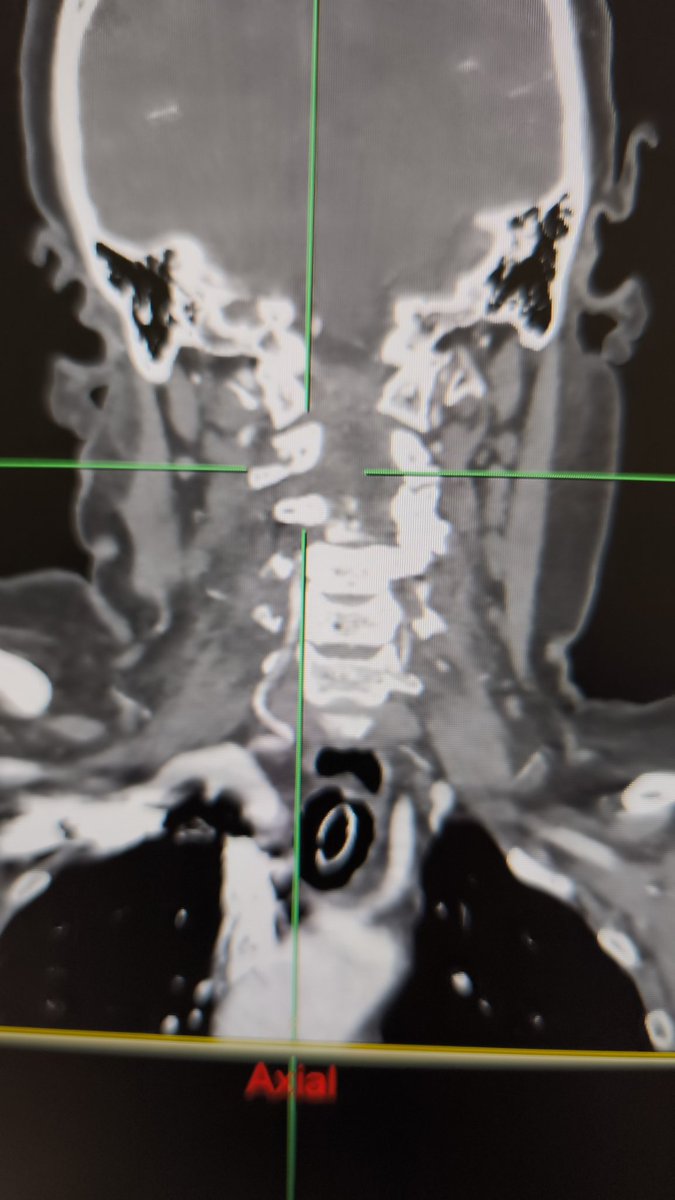

Ruptured cerebral arteriovenous malformation (#AVM), S&M grade IV

#Embolization + #Surgery

Complete Removal !!

Great team !!

Dr. Alberto Blanco (NSG)

Dr. Raquel Alcaraz (AN)

Dr. Raquel Tolos (AN)

Dr. Nerea Joshua (Neurophysiol)

@Sremollo

@IsaRCaamano

Rosa García-Sort (INR Nurse)